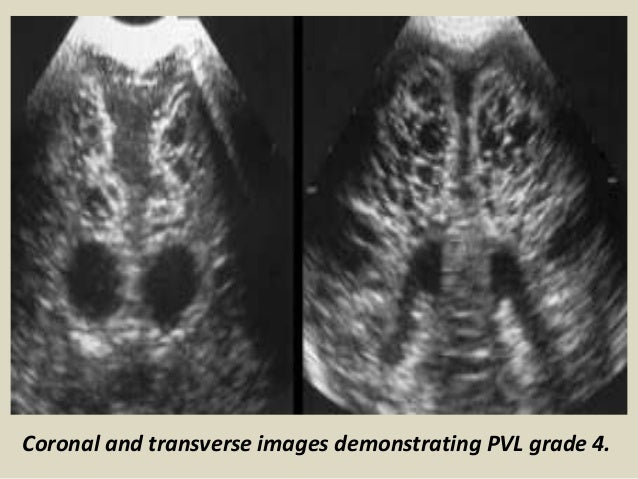

25. 25. Coronal and transverse images demonstrating PVL grade 4.

26. 26. Coronal and transverse images demonstrating PVL grade 4.